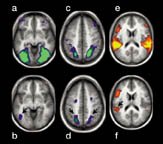

Images of brain show areas that become most active during perception of pictures (a and c, in green) and sounds (e, in yellow).